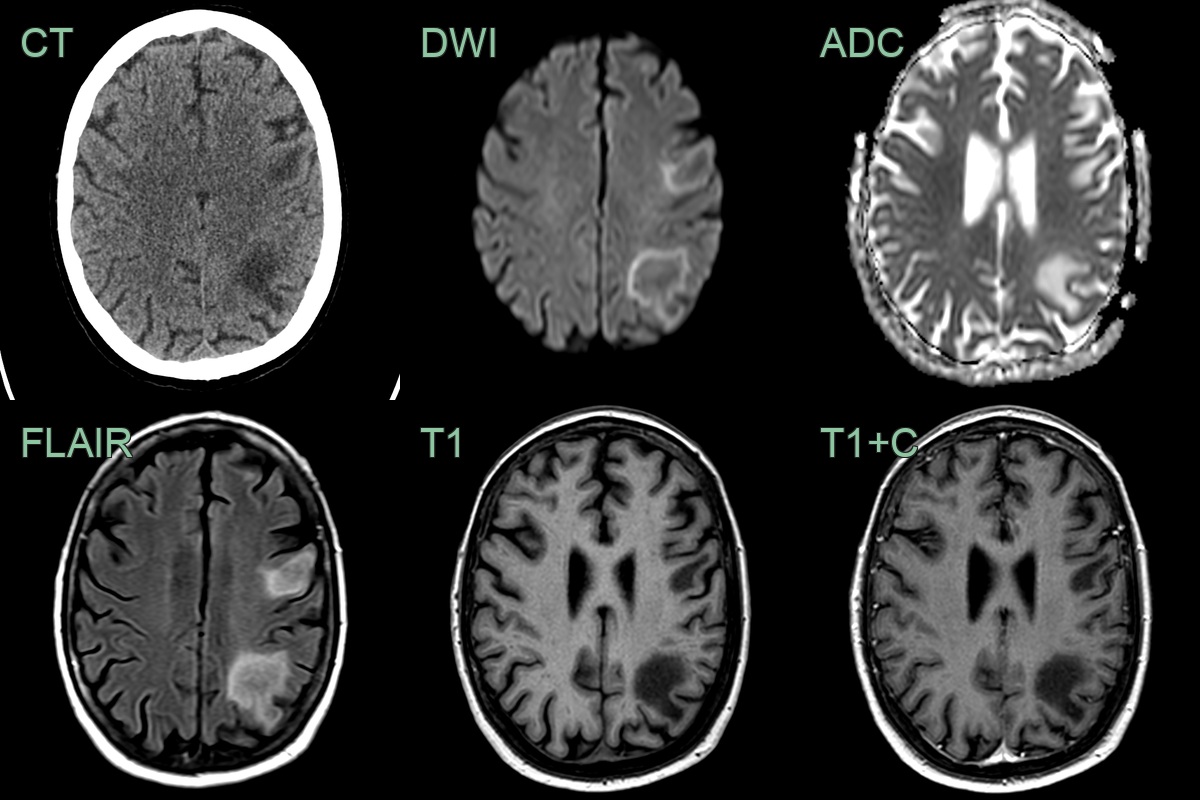

- A 40-year-old patient who had recently underwent CAR-T treatment for lymphoma presented after a 2 week history of headache and photophobia.

- MRI showed a large confluent subcortical region of T2-hyperintensity with a subtle rim of relative diffusion restriction and enhancement.

- Biopsy confirmed PML.

- On follow-up imaging 2 years later, following successful remission of lymphoma, the region matured into a region of gliosis.